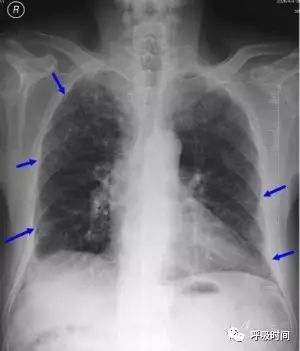

图片

图 11 肺纤维化病变影——弥漫性特发性肺间质纤维化。双肺胸膜下可见网状影及条索影(蓝箭头)